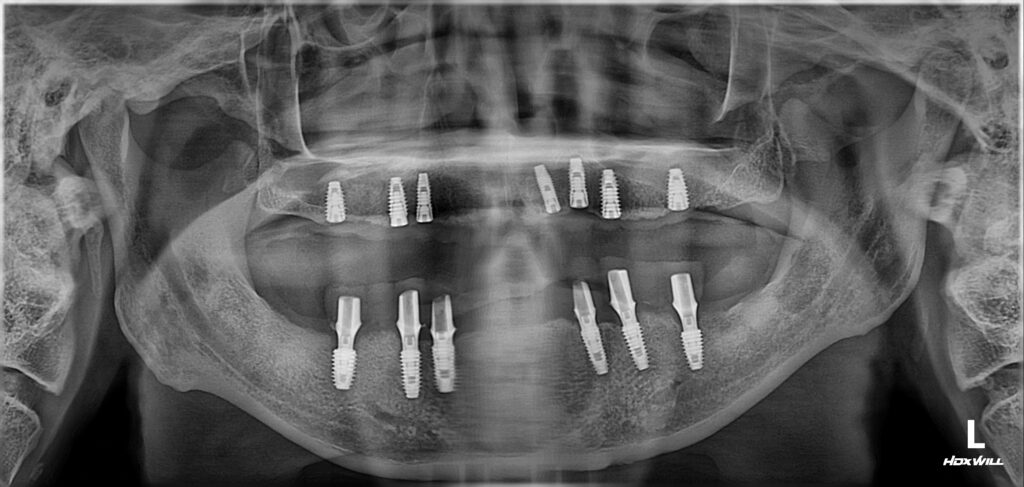

아래턱에 먼저 여섯 개 임플란트를 심었고요.​

다음에 오셨을 때 위턱에 7개 임플란트를 심었습니다.

전체 임플란트를 진행할 때

위에는 최소 7개가

아래에는 최소 6개가 필요합니다